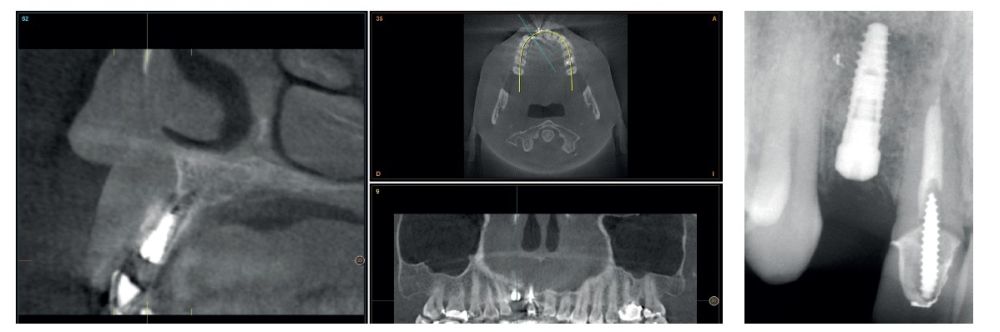

Four months later, a new dental cone-beam is performed to quantify the gain obtained in width with the regenerative procedure. It is observed in the sectional cut that a crest width of more than 7 mm and a complete regeneration of the alveolar ridge has been achieved, allowing the insertion of a new dental implant in the adequate position (Figure 10). In the surgical reentry, the information of the Cone-Beam is verified with a total integration of the graft material, as shown in the clinical images at the time of lifting the flap for the insertion of the implant (Figures 11 and 12). The microscrew is removed and the implant is placed, which is performed by vestibular compression of the graft to gain in this manner even more contour in this area (Figure 13). The implant is left in a surgical phase, with a low healing abutment that allows a subsequent location of the same without an aggressive soft tissue surgery when the construction of the prosthesis is initiated. The provisional crown remains as an extension from the tooth 1.1.